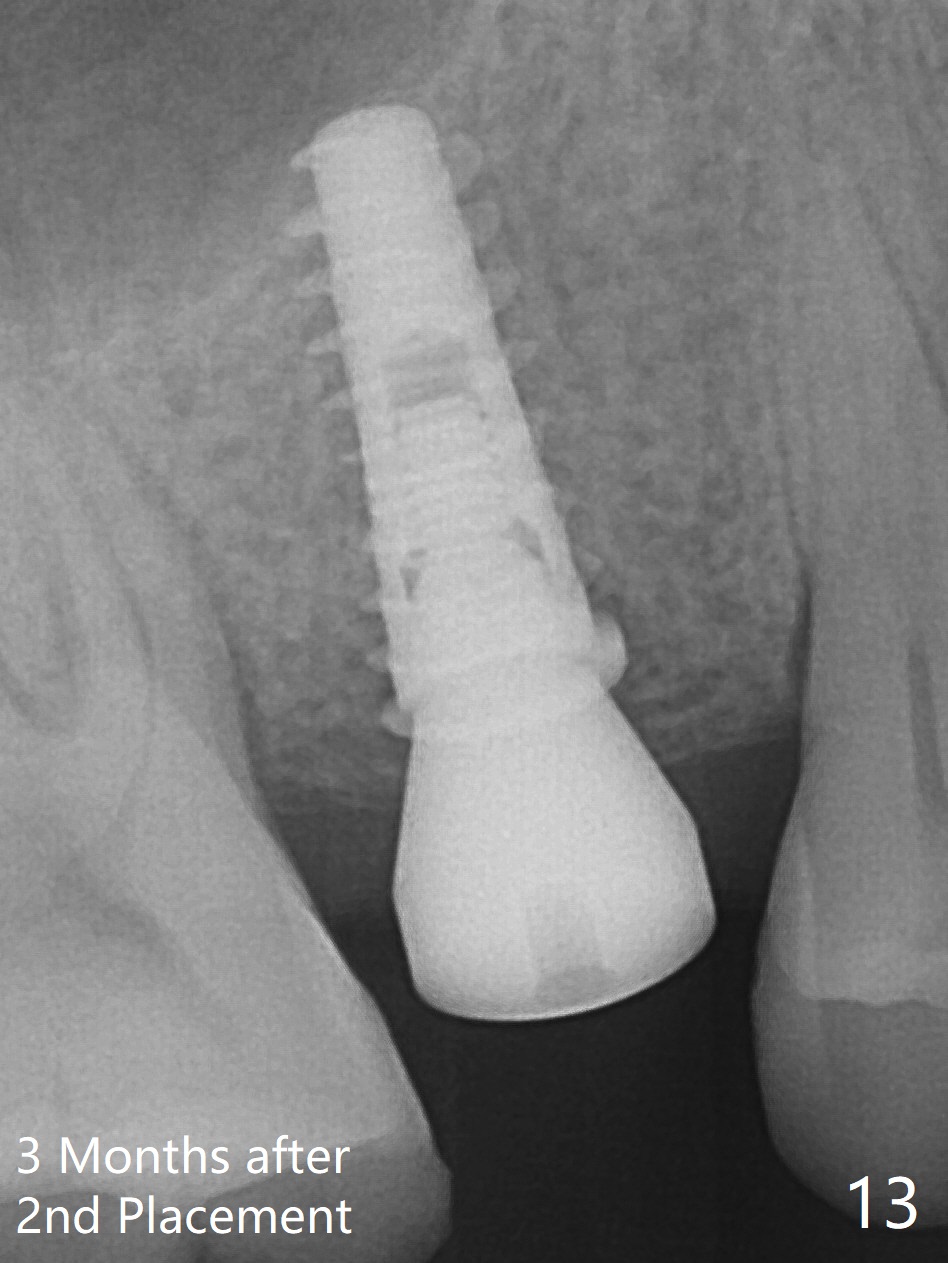

A 47-year-old man returns emergently with subgingival fracture of the lingual (L) cusp of the tooth #4 (Fig.1-3).  After extraction (no bony defect) without drilling, a 4x11 mm dummy implant is placed as a tap drill with satisfactory stability (Fig.4,5).  To get subcrestal placement, a shorter (4x9 mm) implant is inserted with insertion torque of < 35 Ncm.  In retrospect, a larger implant (4.5 mm) would be better in term of primary stability.  After allograft placement into the buccal and lingual gaps, a 4.5x4(4) mm abutment is placed for an immediate provisional.  There is a peri-implant gap 7 months postop (Fig.7<, as compared to the implant at #2 (6 months postop)) .  When the loose abutment is being retightened, the patient feels pain, although the gingiva appears healthy (Fig.8).  A larger implant should have been used; the abutment should have been removed.  The implant dislodges while the abutment is untightened 8 months postop.  The osteotomy is found intact.  A 4.5x11 mm dummy implant is placed 2 mm subgingival with 20 Ncm (Fig.9).  When a 4.5x11 mm definitive implant is placed 3 mm subgingival (Fig.10,11), torque reaches 50 Ncm.  A 5.5x3 mm healing abutment is placed.  Three months postop, the implant is stable (Fig.12,13) and impression is taken.